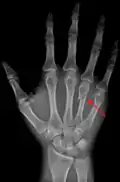

Fourth metacarpal of the left hand (shown in red). Palmar view.

The fourth metacarpal. (Left.)

The fourth metacarpal bone (metacarpal bone of the ring finger) is shorter and smaller than the third.

The base is small and quadrilateral; its superior surface presents two facets, a large one medially for articulation with the hamate, and a small one laterally for the capitate.

On the radial side are two oval facets, for articulation with the third metacarpal; and on the ulnar side a single concave facet, for the fifth metacarpal.